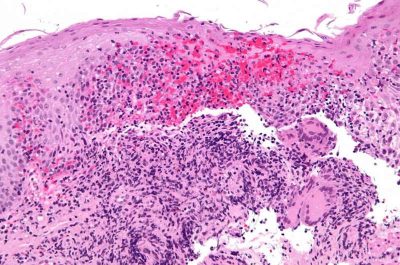

Malattia di Crohn-immagine credit public domain.